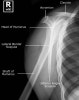

4. Shoulder Lateral view